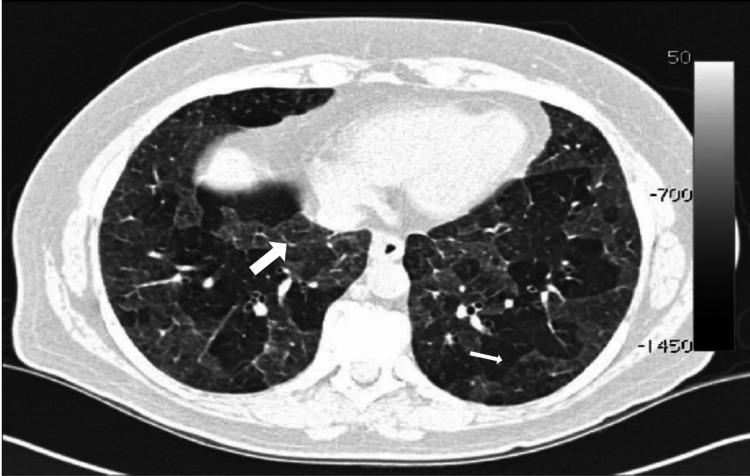

Introduction Interstitial lung diseases (ILDs) primarily affect the interstitium, an alveolar wall tissue between the capillary endothelium and the alveolar epithelium. The term 'interstitial,' however, is misleading since alveolar spaces, peripheral airways, and vessels can be involved in most of these disorders.They often require a multidisciplinary diagnosis i.e., an integration of clinical, radiological, and pathological findings. A chest radiograph is relatively insensitive because of nonspecific patterns. Generally, these disorders can progress to irreversible pulmonary fibrosis and are an important cause of morbidity and mortality. It is critical to make a prompt and accurate diagnosis of the underlying causes so that patients can be managed appropriately. ILD is subdivided into idiopathic interstitial pneumonia, of which idiopathic pulmonary fibrosis (IPF) is one subset, and diffuse parenchymal lung diseases, which may be secondary to a variety of occupational or environmental exposures or others. They can complicate multiple rheumatic or connective tissue diseases (CTDs). Apart from ILD, other forms of lung damage involving the pleura, vasculature, airways, and lymphatic tissue can complicate CTDs. Aims  Aims include studying the role of high-resolution computed tomography (HRCT) in diagnosing various ILDs based on morphologic patterns, evaluating the correlation between ILD and various connective tissue disorders and the prevalence of complications in such patients, and evaluating the association of smoking with various ILDs. Methods This is a retrospective study in which HRCT thorax was performed on a 128-slice Philips CT scanner machine on 50 patients from December 2020 to February 2022 in SVP Hospital, Ahmedabad. No age or gender bias was followed. Result Out of 50 patients studied, 19 (38%) patients had the usual interstitial pneumonia (UIP) pattern and 12 (24%) had the nonspecific interstitial pneumonia (NSIP) pattern. These two were the most common among all ILD patterns. Other patterns found were hypersensitivity pneumonitis (5; 10%), respiratory bronchiolitis-related ILD (3;6%), and organizing pneumonia (2; 4%). In nine patients, the morphologic pattern was either subtle (3; 6%) or mixed (6; 12%), and the final diagnosis remained inconclusive; patients were advised clinical correlation and biopsy. Eleven (22%) patients had a history of smoking. Among smokers, the most common pattern was UIP while all patients with respiratory bronchiolitis (RB) ILD had a history of smoking. Fourteen (28%) patients showed a positive association with CTD. Among them, rheumatoid arthritis (RA) was the most common CTD and the most common pattern among RA patients was UIP. Ten (20%) of patients developed pulmonary arterial hypertension, of which two patients who had connective tissue disorder developed pulmonary arterial hypertension at a young age (24 years). The rest of the patients who developed pulmonary arterial hypertension were above 45 years of age. Among these, two were smokers. Conclusion HRCT plays an important role in the diagnosis of ILD on the basis of various morphological patterns. CTD plays a significant role in the development of ILD. UIP is the most common ILD among patients with a smoking history and RA. NSIP Is the most common in patients with CTD other than RA. Pulmonary arterial hypertension (PAH) develops early in patients with CTD. There is a significant risk of the development of PAH in patients with chronic ILD.

在研究的50例患者中,19例(38%)表现为普通型间质性肺炎(UIP)模式,12例(24%)表现为非特异性间质性肺炎(NSIP)模式。这两种是所有ILD模式中最常见的。发现的其他模式包括过敏性肺炎(5例;10%)、呼吸性细支气管炎相关的ILD(3例;6%)和机化性肺炎(2例;4%)。9例患者的形态学模式不明显(3例;6%)或为混合型(6例;12%),最终诊断仍不明确;建议患者进行临床关联和活检。11例(22%)患者有吸烟史。在吸烟者中,最常见的模式是UIP,而所有呼吸性细支气管炎(RB)ILD患者都有吸烟史。14例(28%)患者显示与CTD呈正相关。其中,类风湿关节炎(RA)是最常见的CTD,RA患者中最常见的模式是UIP。10例(20%)患者发生了肺动脉高压,其中2例患有结缔组织病的患者在年轻时(24岁)发生了肺动脉高压。其余发生肺动脉高压的患者年龄在45岁以上。其中,2例为吸烟者。